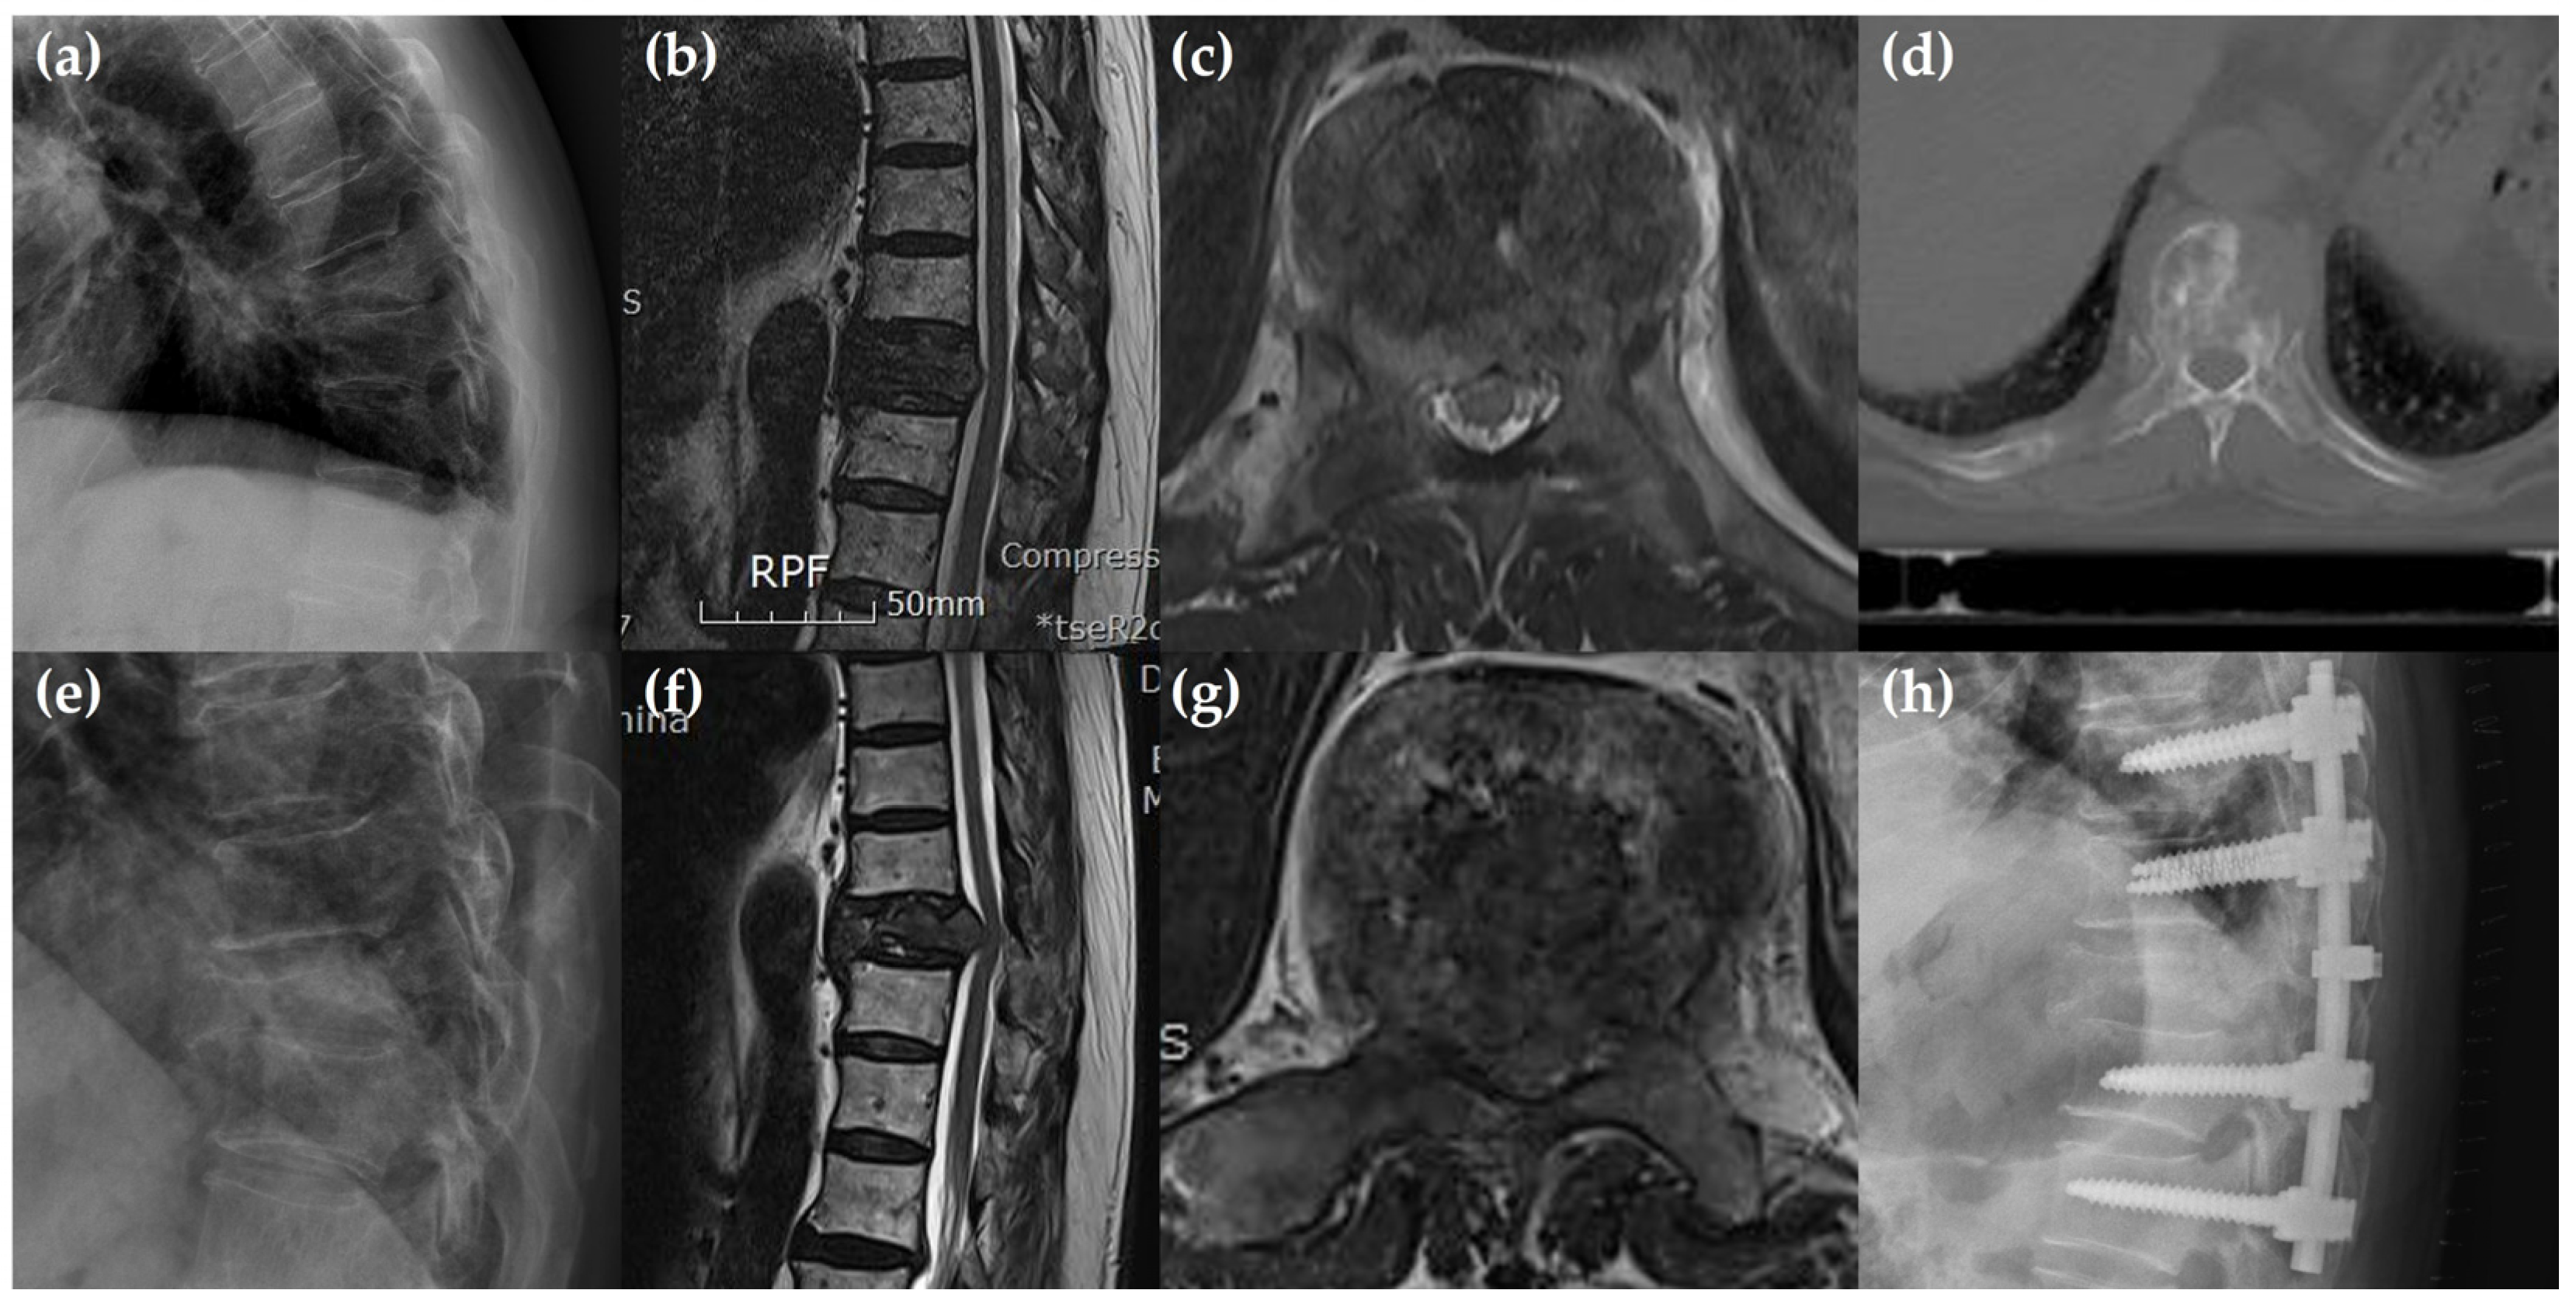

3.3. Preoperative Radiological Findings

| Preoperative radiological findings | |||

| -Cord compression | 45 (89.4) | 30 (67.6) | 0.203 |

| -Pathologic fracture | 42 (89.4) | 20 (58.8) | 0.001 * |

| -Vertebral body collapse | 0.308 | ||

| -50% < | 28 (59.6) | 24 (70.6) | |

| -50% > | 19 (40.4) | 10 (29.4) | |

| -Posterolateral involvement | 42 (89.4) | 31 (91.2) | 0.787 |

| -Anterior dura compression | 45 (93.6) | 29 (79.4) | 0.099 |

| -Tumor characters | |||

| -Osteolytic lesion | 37 (78.7) | 21 (61.8) | 0.095 |

| -Osteoblastic lesion | 2 (4.3) | 5 (14.7) | 0.099 |

| -Mixed lesion | 8 (17.0) | 8 (23.5) | 0.468 |